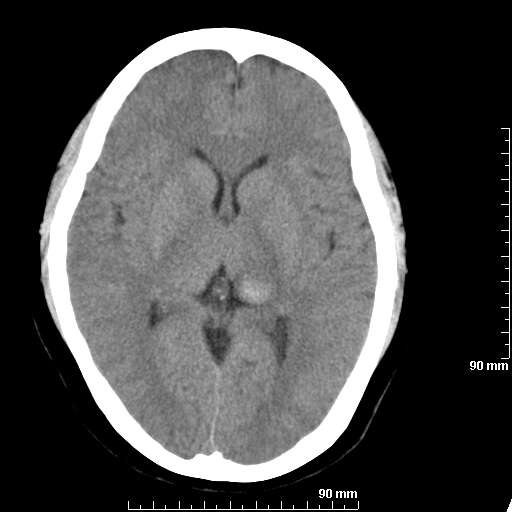

我院西门子单排CT由于一零件受损而产生的伪影.

哈哈,都不是。是虑线器fiter裂损。大家没想到吧。

哦,跟脑出血有点像哦

形状不规则,边缘模糊。比较特殊的一种伪影哈!

这种伪影很常见!伪影应该是在视野的中心的。

西门子的虑线器fiter裂损这才是很难见的问题,GE的最常见

虑线器老化,中间崩裂一块掉了